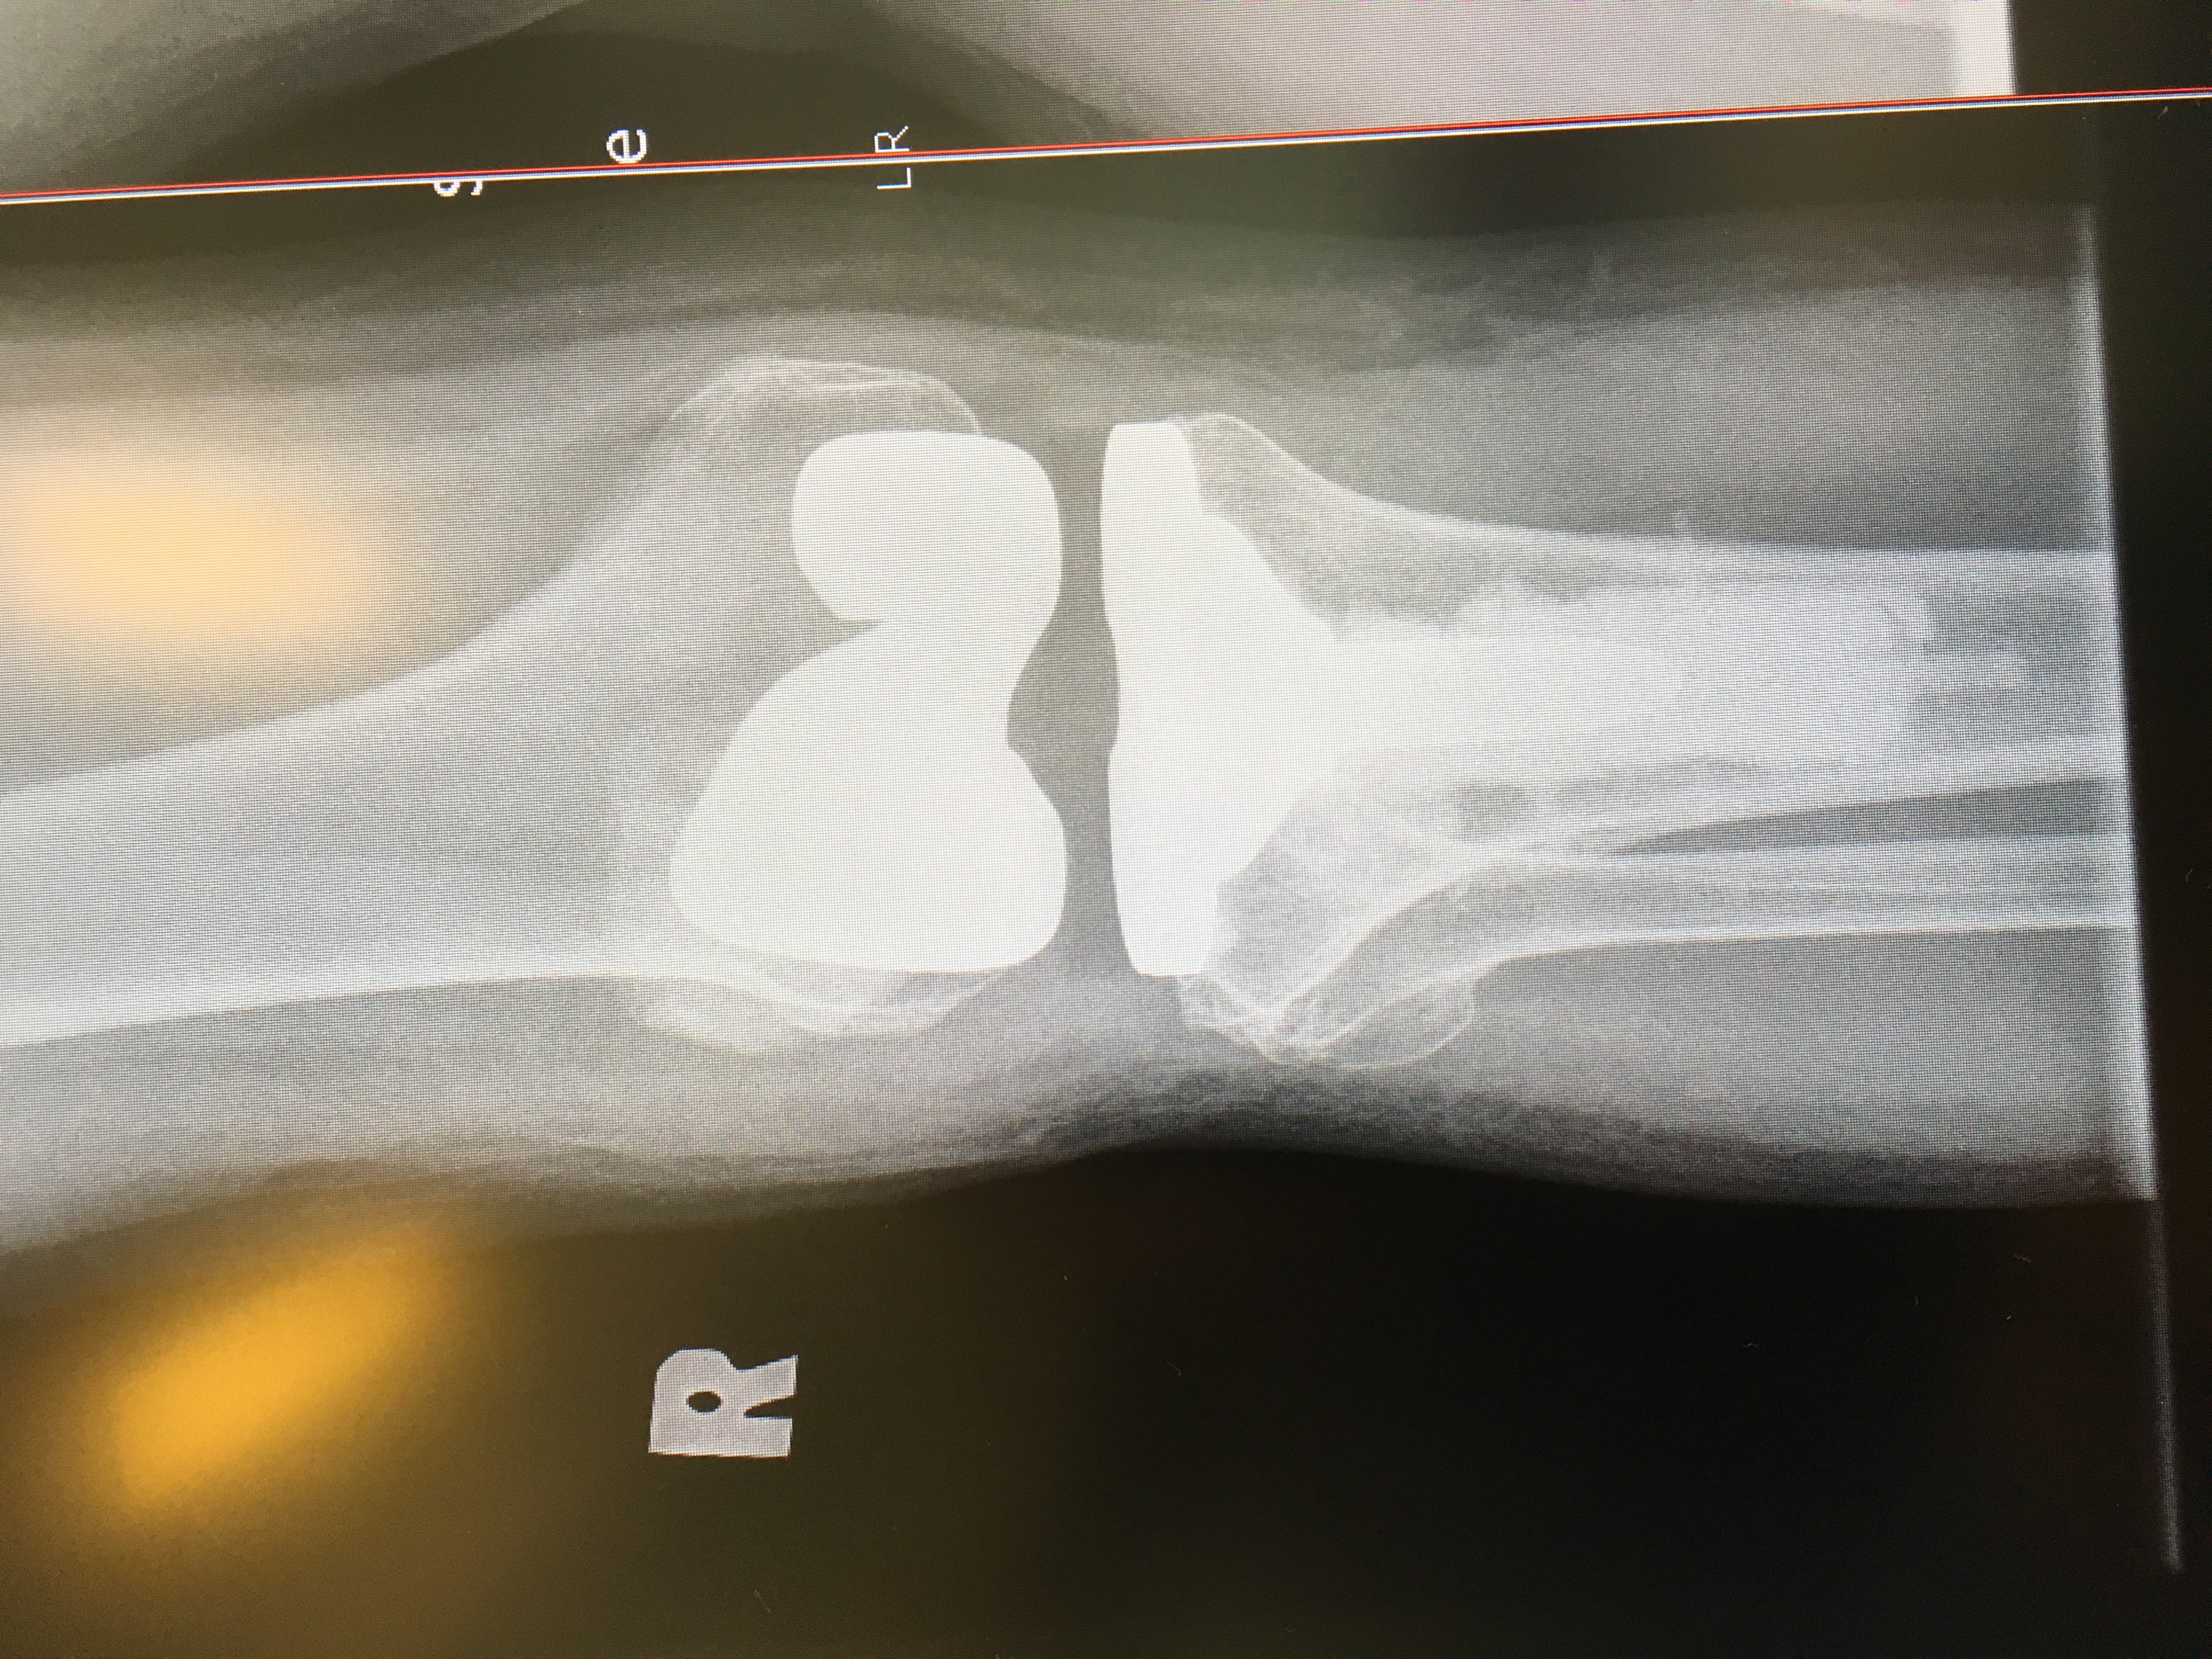

My Wife has problems with both knees, Dr Wood was recommended by several friends. We Had an appointment with Dr Wood and found him to be very personable and explained things in a way that we could understand. All the options were talked about and We think the best plan was initiated. We Liked Dr Wood a lot and would definitely recommend him for your orthopedic needs.

I needed THREE knee revisions after Dr. Wood’s full knee. Do NOT be fooled by his many hundreds of knee revisions — he works two ORs at once and cuts corners. He gave me a CR knee which requires a PS ligament I don’t have, BUT it’s a faster install. He also gave me a size 5 and I needed a size 7. Today, after seven years of pain and knee instability, I finally have a stable knee — NO thanks to Dr. Wood. I would NEVER go to him again for anything, especially NOT knee surgery!

Dr. Wood will never be trusted with another family member or friend's life if I have anything to say about it. He operated on my husband 4 times, with the last being a knee replacement. The first three times, he'd go in with a plan and then change it and I firmly believe he forced the knee replacement by taking out all the cartilage on the back of the knee cap so it was the only choice. He left my husband in more pain than he ever started with. With the knee replacement, he came out of surgery with PE and DVT - his sats were... read more